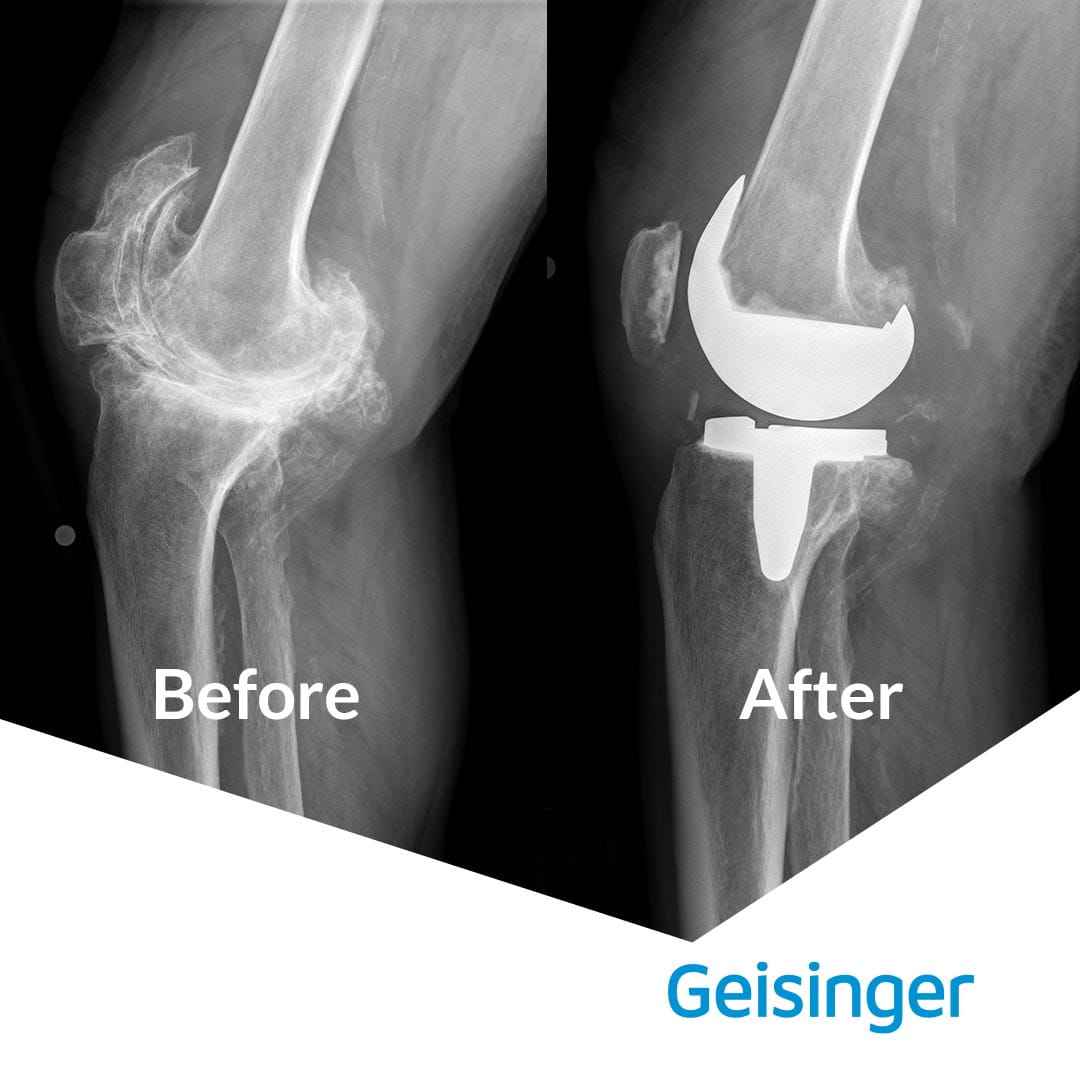

“I had arthritis in both knees. The right knee was especially bad because of an old football injury,” Mr. Cooper explains. “There were numerous bone spurs and one was the size of a golf ball. The X-rays were really something — it didn’t even look like a knee.”

Knee Replacement Images-Before and After.